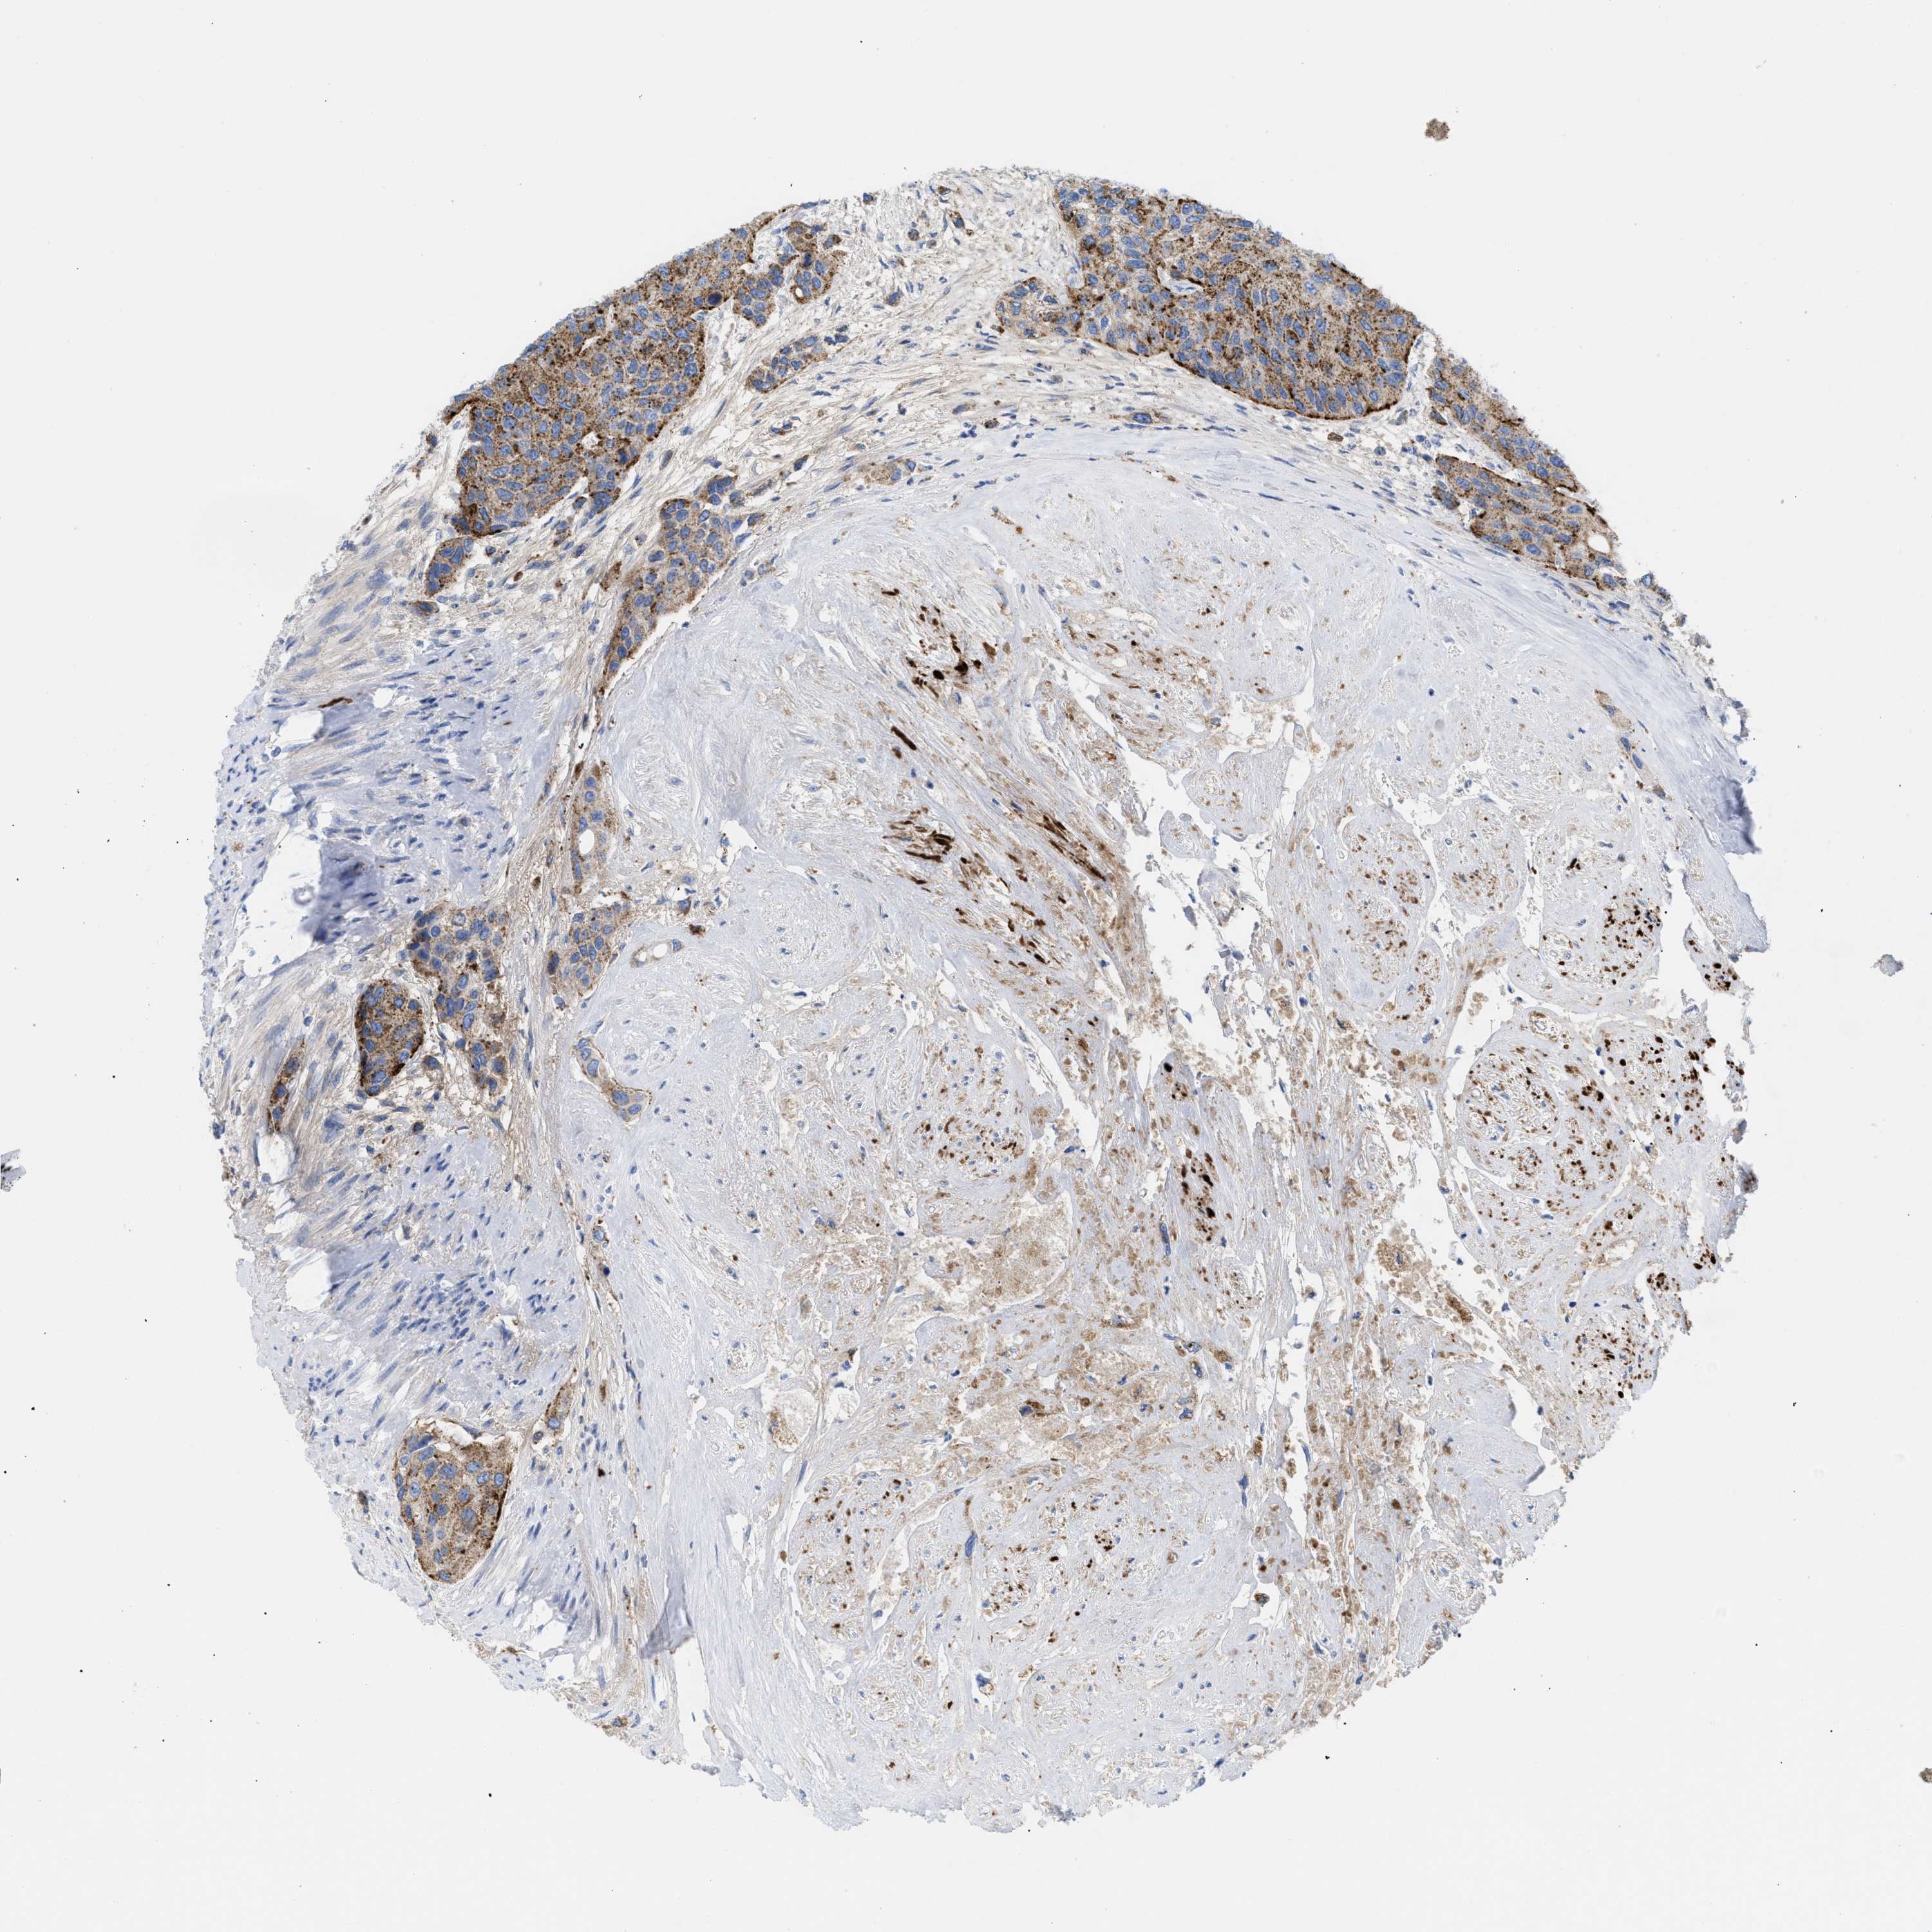

UROTHELIAL CANCER - Protein expressioni

A mouse-over function shows sample information and annotation data. Click on an image to view it in a full screen mode. Samples can be filtered based on level of antibody staining by selecting one or several of the following categories: high, medium, low and not detected. The assay and annotation is described here.

Antibody stainingi

Antibody staining in the annotated cell types in the current human tissue is reported as not detected, low, medium, or high, based on conventional immunohistochemistry profiling in selected tissues. This score is based on the combination of the staining intensity and fraction of stained cells.

Each image is clickable and will lead to virtual microscopy that enables deeper exploration of all samples and also displays staining intensity scores, fraction scores and subcellular localization as well as patient and tissue information for each sample.

Antibody HPA018036

Antibody HPA061701

Staining

High

Medium

Low

Not detected

Intensity

Strong

Moderate

Weak

Negative

Quantity

>75%

75%-25%

<25%

None

Location

Nuclear

Cytoplasmic/membranous

Cytoplasmic/membranous,nuclear

Urothelial carcinoma, Low grade

Urothelial carcinoma, High grade

Urothelial carcinoma, NOS